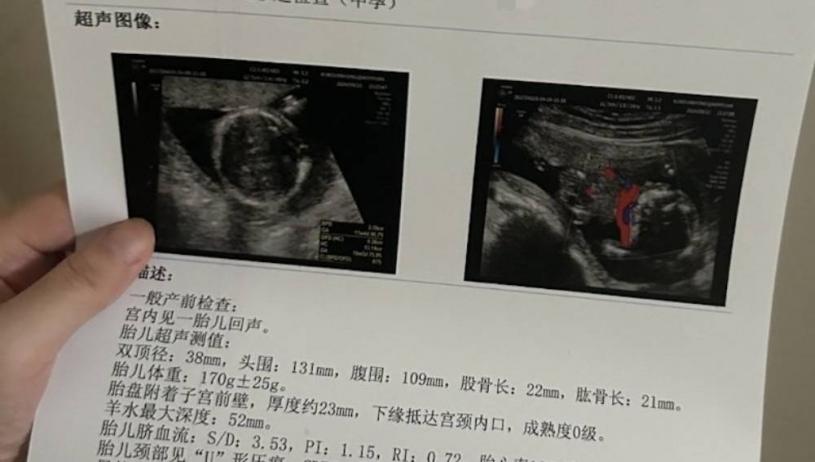

她告訴澎湃新聞,代孕機構事先承諾的代孕補償是24萬元,分階段支付。她被安排到私立醫療機構產檢,第一個月在昆山某門診部產檢,後來轉到某醫院。據她回憶,產檢時,其他代孕媽媽用別人的身份證掛號,小溪用自己的身份證,但是做產檢的醫療機構都沒有給她建檔。在懷孕5個多月後,11月6日小溪意外流產,11日接受清宮手術,接下來就如上述給人趕走了。